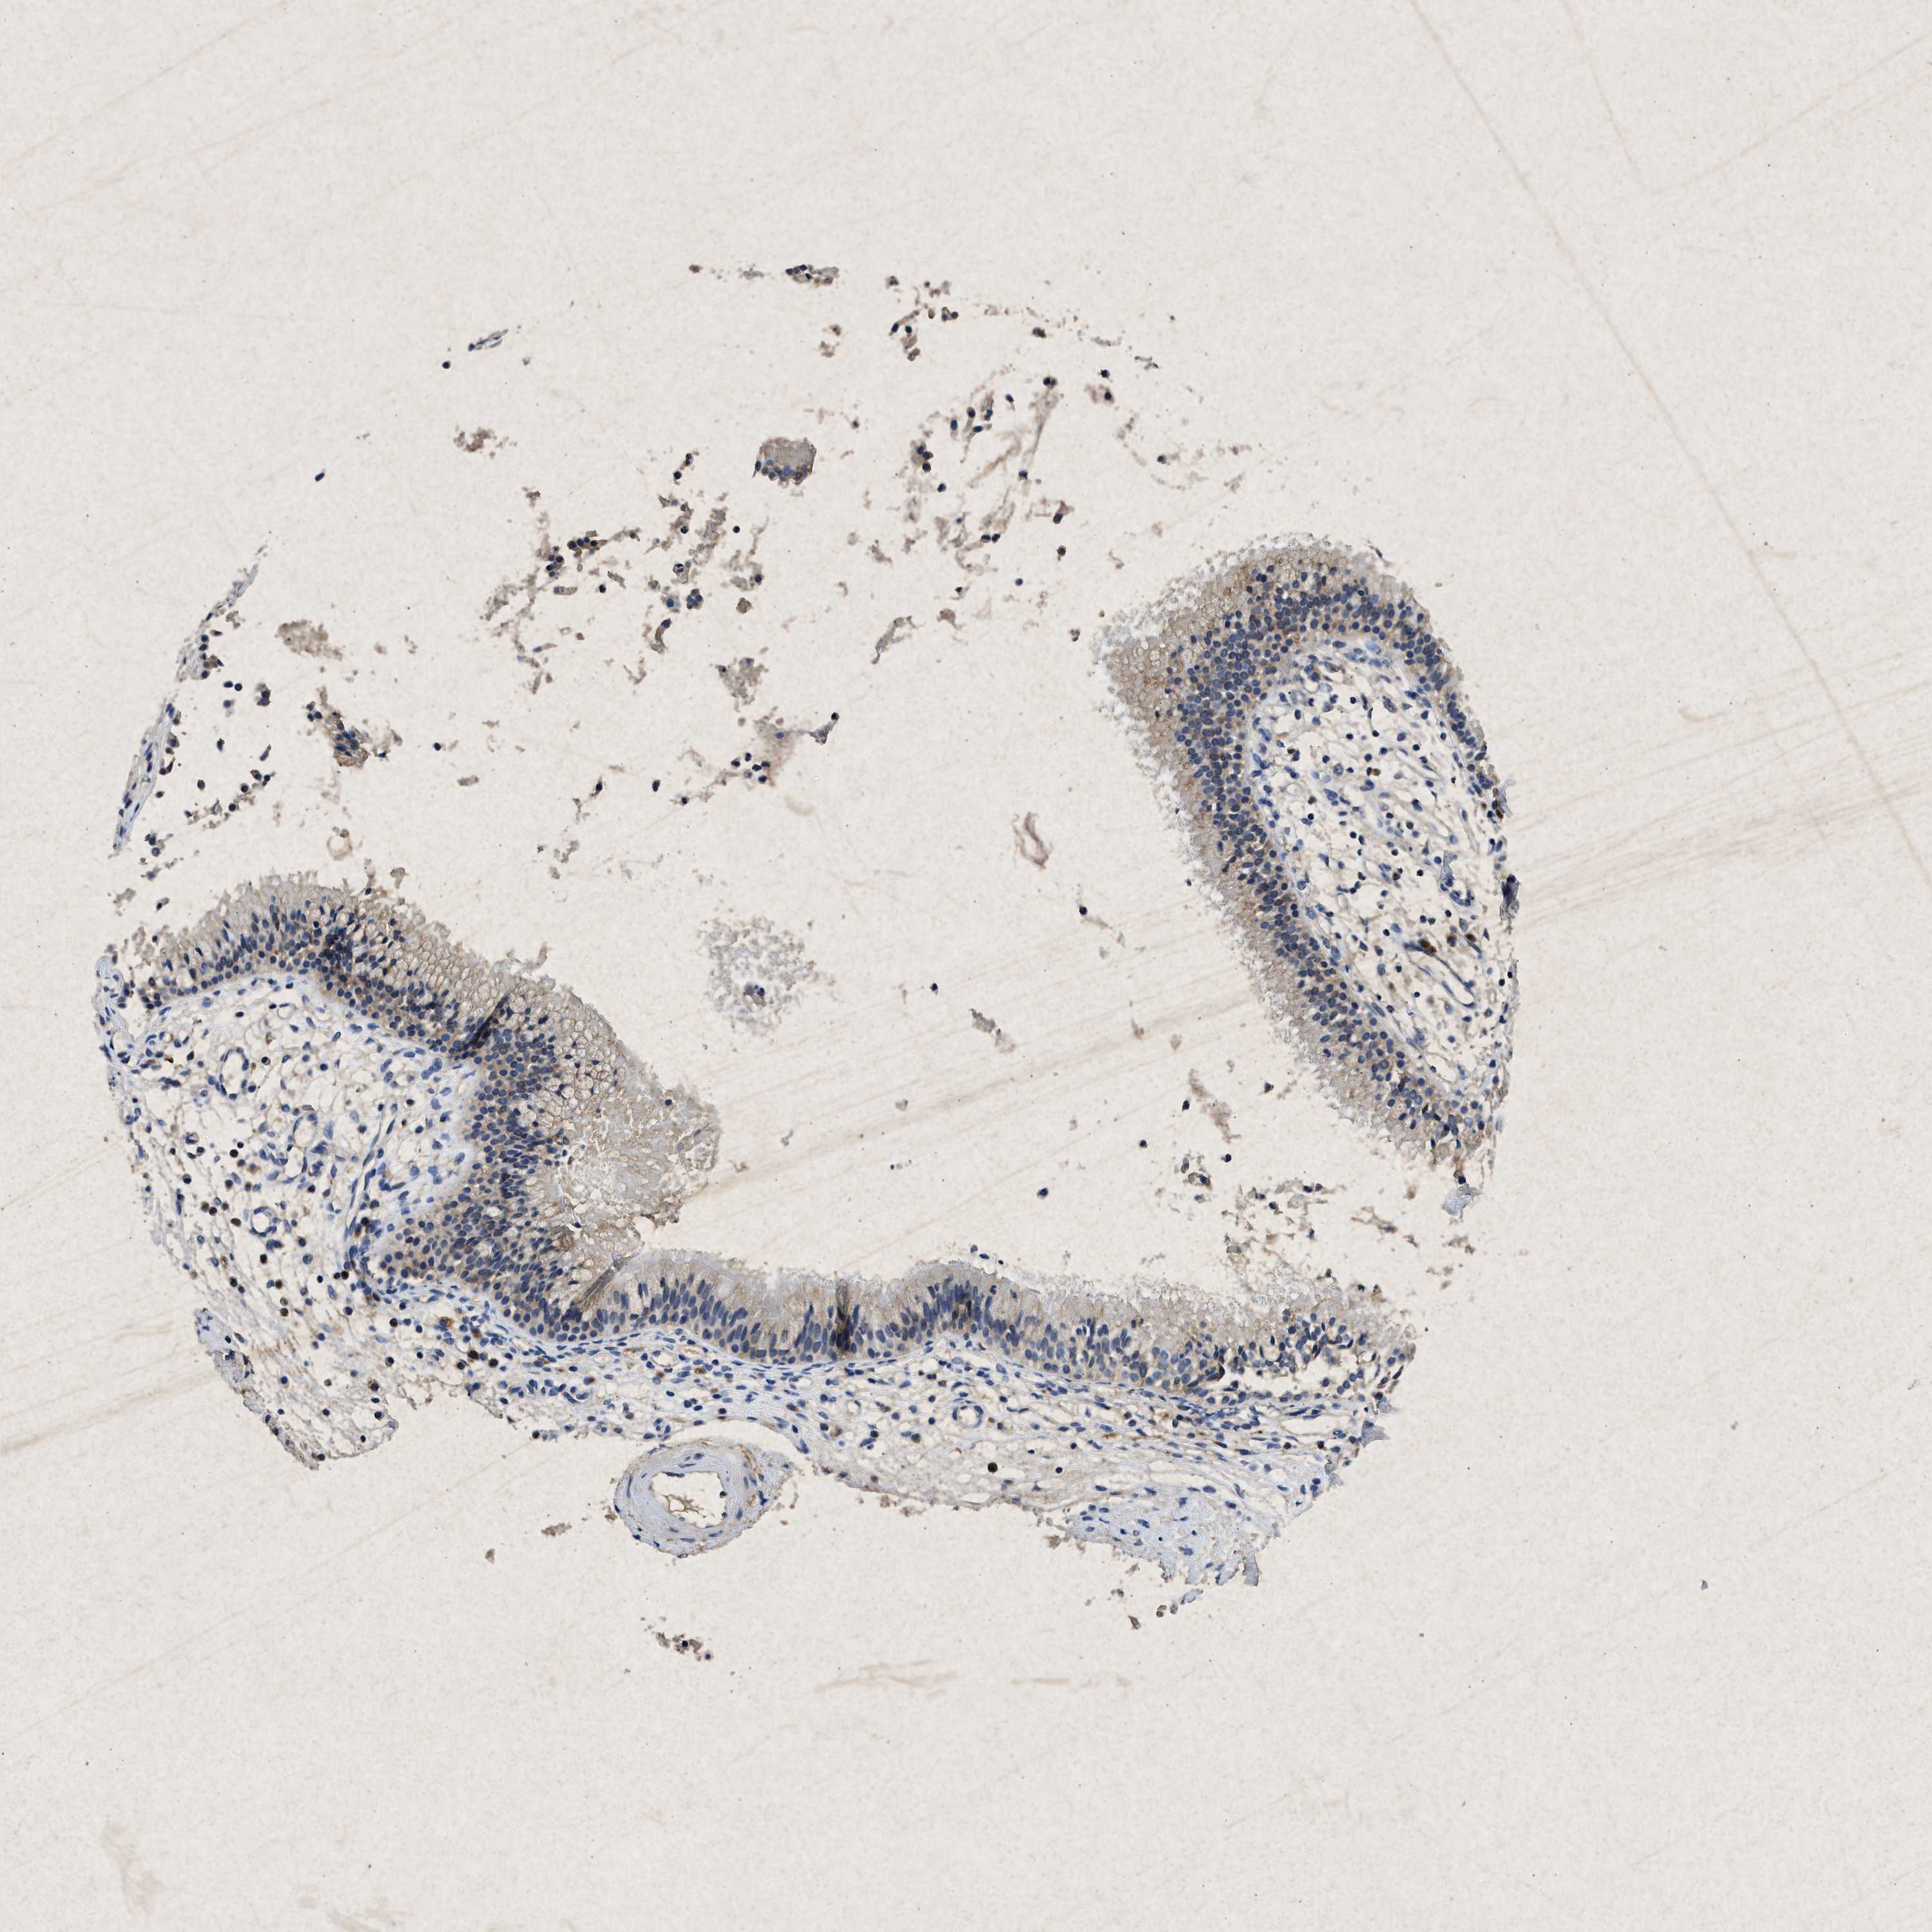

KCNQ1